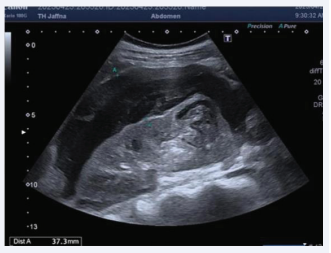

Ultrasound Scan of the abdomen depicted large intracapsular haematoma with a small aneurysm in the inter polar region of right kidney (Figure 1, 2). Ultrasound excluded any uterine bleeding or focus of infection.

Ultrasound Scan of the abdomen.

Figure 2: Ultrasound Scan of the abdomen.